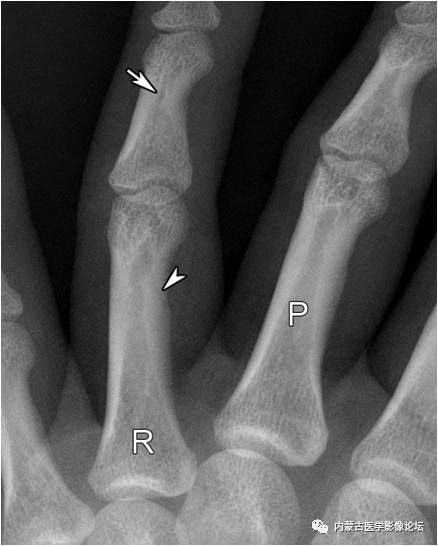

指骨正常骨突与骨嵴:白箭所示为肌腱附着的骨突与骨嵴,不应误为骨痂或骨膜增生。R:环指,P:近节指骨,M:中节指骨,D:远节指骨。